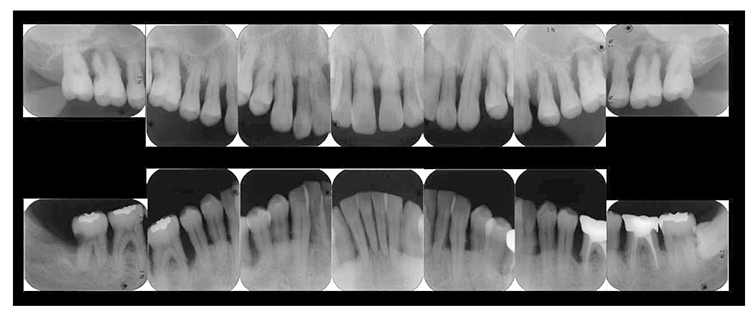

(3) X-ray findings

At the first visit, the findings showed moderate to advanced horizontal alveolar bone resorption in the entire jaw, and advanced vertical bone resorption on 24,36,46, 47. Additionally, on 46,47 were radiolucent findings that were likely associated with furcation involvement, and radiolucent areas on the alveolar bone surrounding the root apex were shown on 16,11,26. Furthermore, distally on 47, radiolucent findings showed caries extending into the dental pulp.(Fig.1c).

Fig 1c

(Fig.1c) Dental X-ray 14 during first visit (June 2007)